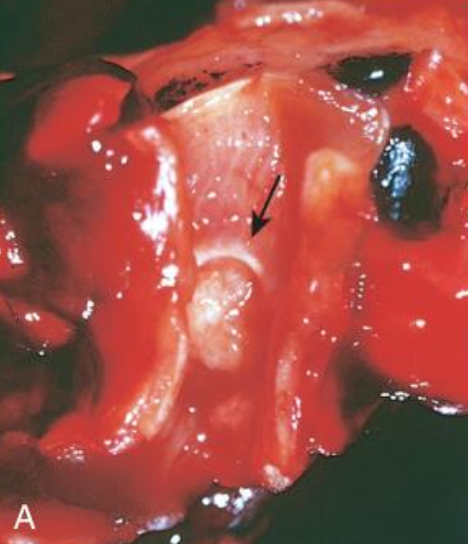

<p>Características de tumores carcinoides <strong>centrales</strong></p><p></p><p></p>

Características de tumores carcinoides centrales

• Digitiformes o polipoides en luz bronquial revestidos por mucosa normal

• < 4mm

• Bronquios principales

• Lesión en botón de cuello de camisa, cuando penetran tejido peribronquial